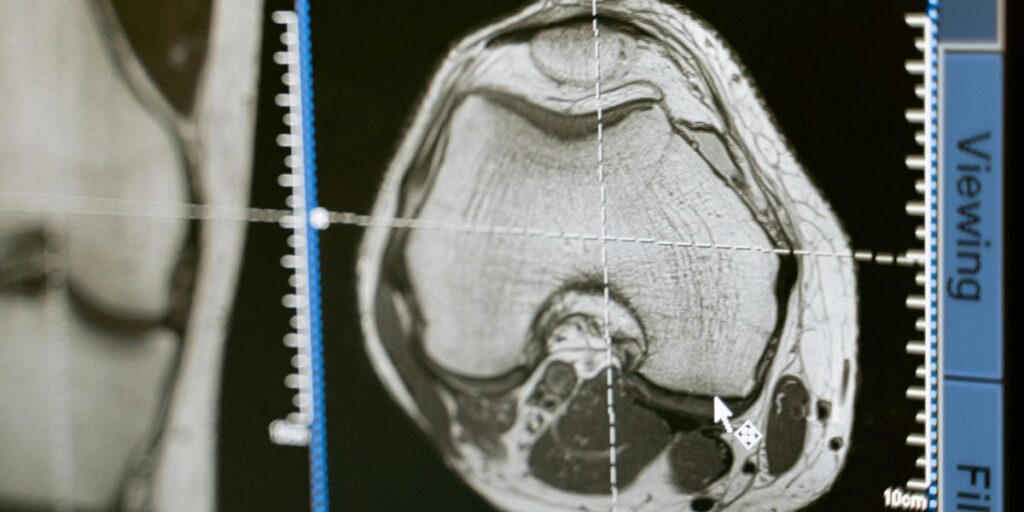

A radiology tech, also called a radiologic technologist or x-ray technician, helps doctors by taking images like x-rays, MRIs, or CT scans. These kinds of images help doctors find and treat problems inside the body.

A radiology tech is a healthcare worker who takes pictures of the inside of the body. These pictures, like X-rays or CT scans, help doctors find injuries, issues and health inner problems. Radiology techs work closely with patients and use special machines to get clear images.

Radiology techs are also called with the radiologic technologists or imaging technicians. They follow safety steps to protect patients from too much radiation and make sure the images are done correctly